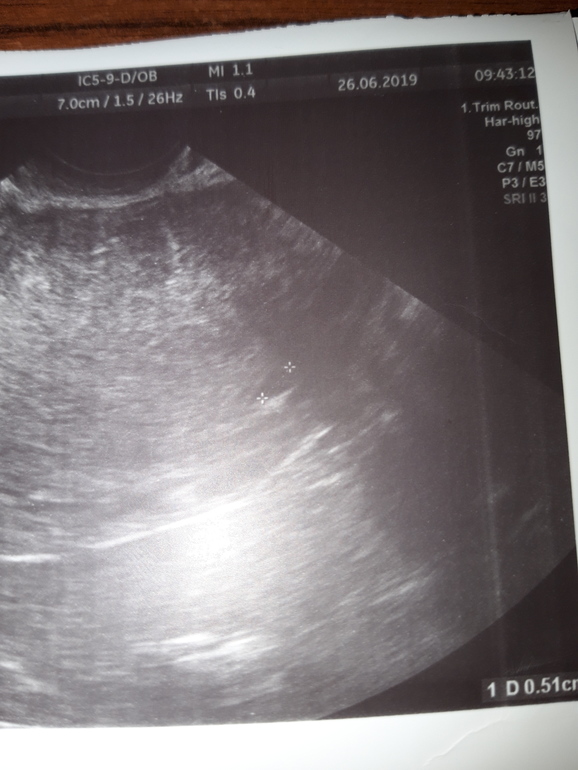

Девочки,понесло меня короче на повторное узи,муж настоял,так как вчера ночью сильно болел правый бок,не спала всю ночь. В общем,2 дня назад на узи видели пятнышко размером 3-4,сегодня это пятнышко было уже побольше,5 с лишним мм,врач узи говорит что непонятно что это,спросила про тесты,так я говорю они почти сравнялись,ну ладно посмотрела желтое тело и нашла размером 22,крутила вертела датчиком,начала говорить что на пя не похоже и возможно пя еще в трубе,девочки как это??? Я ей говорю как так,тесты то не пустые значит где то да прикрепился плод,говорю ей ведь хгч вырабатывается после имплантации,на что она мне говорит что хгч вырабатывается с момента зачатия🙄🙄🙄что за бред? Спросила есть ли задержка,да уже второй день. На что она меня вновь спрашивает принимаю ли я какие нибудь гормоны,отвечаю что пью дюфастон,а она мне возмущенно "конечно на нем у вас месячные не пойдут"🤦🏼♀️.Вопрос,почему они у меня должны пойти при положительных тестах и довольно не плохих показателях узи??? Девочки то ли я туплю то ли много знаю,что это за бред с хгч,везде ведь пишут что он вырабатывается после имплантации,как это все понимать? Добавлю,в предыдущие беременности когда я ходила на узи мне врачи так же говорили когда пя не видели в матке,типо еще по трубам идет. Загляните пожалуйста на снимок,может кто что поймет,еще в прошлую пятницу в матке ничего не было а на понедельник обнаружилось это черное пятно и на сегодня оно увеличилось,что это еще может быть если не плодное яйцо